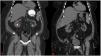

Sodium bicarbonate is a suitable alternative to potassium citrate for patients with kidney problems or other risk factors for hyperkalemia.29Fig. 1 demonstrates the effect of oral dissolution therapy on a patient before receiving therapy (Fig. 1A) and successful dissolution after treatment is completed (Fig. 1B). Dose adjustment for either medication can be made by monitoring urine pH in the doctor's office or at home using nitrazine paper in order to maintain the appropriate pH level for dissolution and also prevent over-alkalinization.8